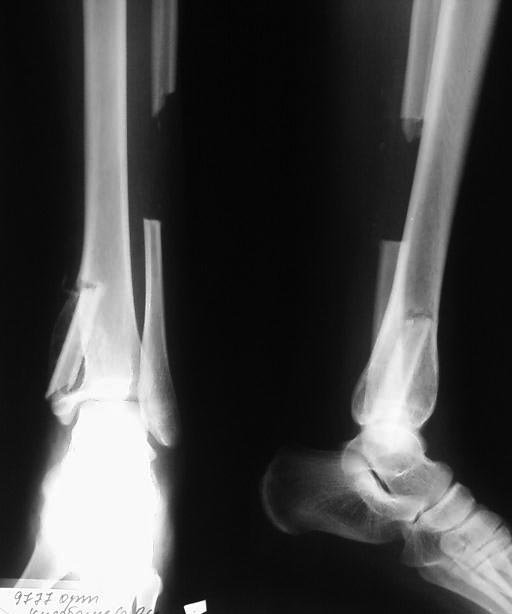

[Ortho] Остеобластокластома

Уважаемые коллеги , спасибо за участие  обсуждения  нашего случая. Мы прооперировали  больную- выполнили  внутреннюю резекцию  очага  опухоли , костная пластика  трансплантатом из малоберцовой кости.Вашему вниманию  предоставляем  снимок.